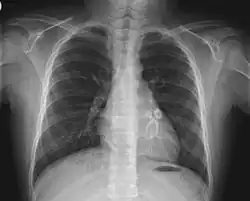

Diagnosis is by specialist clinical evaluation.[59] Diagnostic suspicion may be raised by unexplained persistent fever and clinically concerning symptoms following exposure to COVID-19.[14] Families need to seek immediate medical care, as the child's condition can deteriorate rapidly.[7] Paediatricians' first involvement is often in the emergency department.[49] Early recognition and multidisciplinary referral to paediatric specialists (in intensive care, infectious diseases, cardiology, haematology, rheumatology, etc.) is essential.[13][23][14][19] Examinations may include blood tests, chest x-ray, heart ultrasound (echocardiography), and abdominal ultrasound.[60] Clinicians worldwide have been urged to consider this condition in children who display some or all the features of Kawasaki disease or toxic shock syndrome.[24]